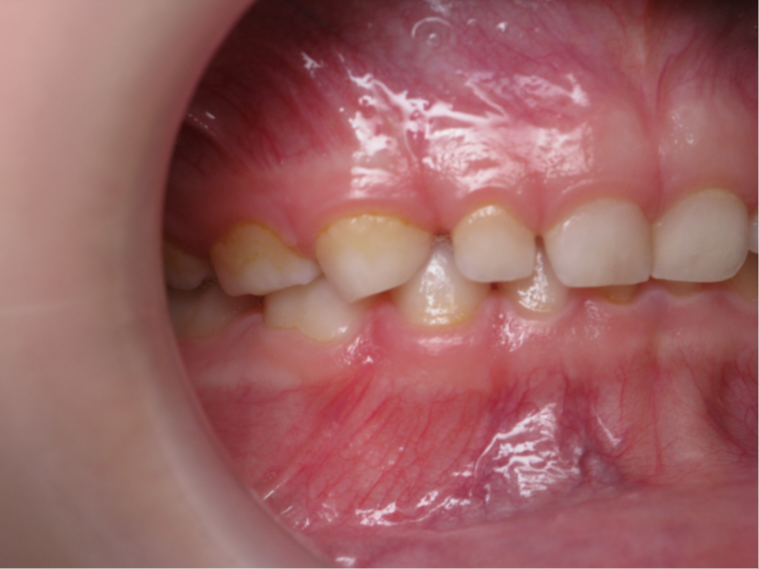

inversion des dents postérieur coté gauche

appareillage mobile pendant 7 mois

bilan début et fin de traitement